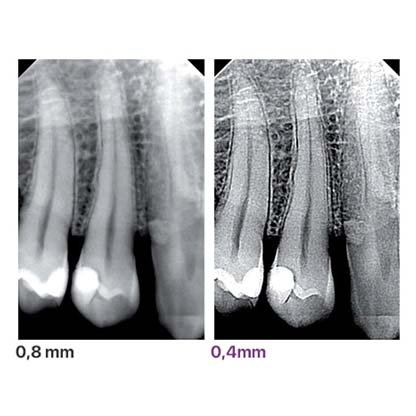

This technology gives sharp images with greater detail and lower exposure times than would be attainable with AC X-ray units, which are characterised by variable emissions.

RXDC - eXTend technology is reliable for all diagnostic needs and always provides high-definition images by adapting to the sensor type.